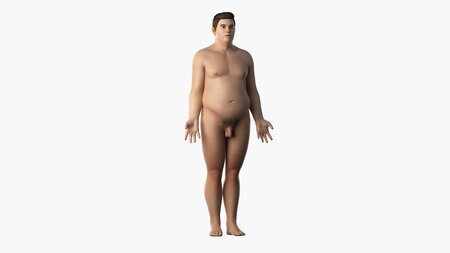

It contains: